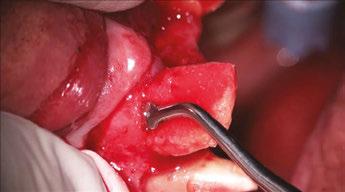

Let’s review a recent case that showcases the rationale and techniques of the top three. It is common to utilize several suturing techniques in surgical closure, especially in larger grafting cases. In the following case, a lateral sinus lift was performed, and all three techniques were used to their full effect. Simple interrupted sutures are used to close small incisions and place tissue margins accurately back in place; horizontal mattress sutures are used to hold membranes in place and relieve tension over the incision line, and running interlocking continuous sutures are used to close longer incisions with watertight closure for maximum healing potential via primary closure.

A patient presented with a failing bridge on the upper left that is supported by three mini implants. The implants directly perforate the sinus and only ~2mm of residual bone height remains on the crest (Figure 8). The mini implants were removed, and a

Figures 7A and 7B: Horizontal mattress sutures are useful for helping to secure membranes in grafting situations and relieving tension in longer span incisions Figures 8A and 8B: The pre-op condition of the patient with mini implants engaging minimal bone and perforating the sinus. The patient’s implant supported bridge was loose and causing discomfort Figure 9: A periosteal biting mattress engages only the periosteum in the buccal vestibule and exit and re-enters on the lingual tissue, helping to secure the membrane tightly over the window and crest